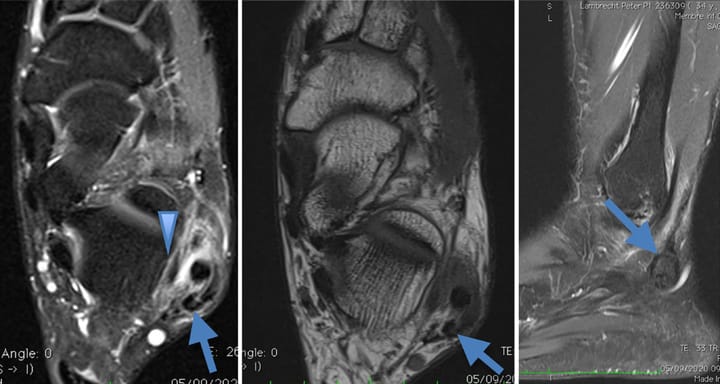

Rhumatologie Prise en charge thérapeutique et principes de rééducation des entorses de la syndesmose tibio-fibulaire inférieure